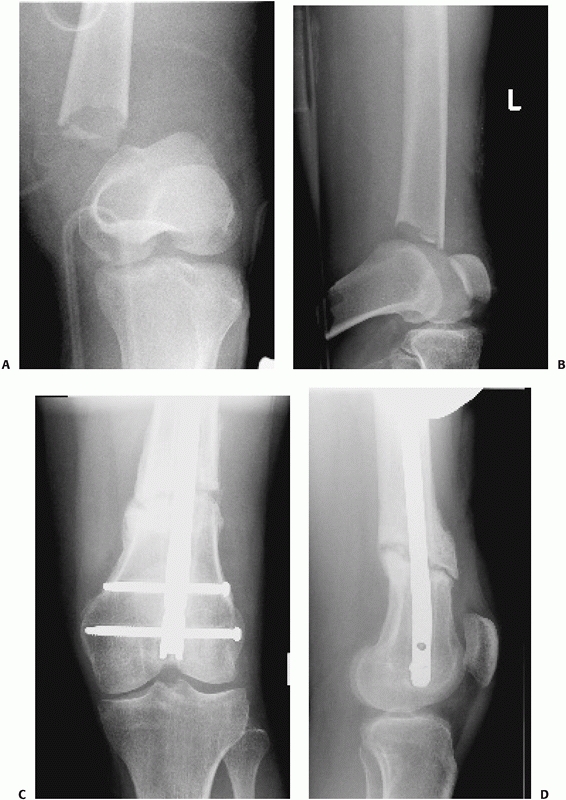

FIGURE 50-9 A comminuted femoral diaphyseal fracture (A)

in a patient with multiple other injuries including a pulmonary contusion, liver laceration, and head injury. Temporary external fixation (B) was rapidly applied initially to provide stability and alignment. Conversion to an antegrade nail 7 days later resulted in uneventful healing (C). |